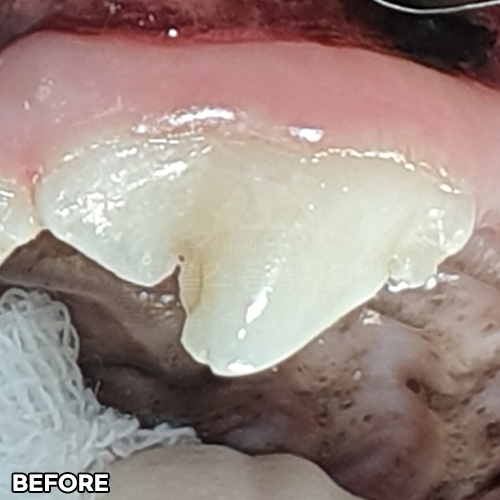

[대형견 마라노이즈 송곳니 레진치료 - 강아지치과 법랑질 저형성증 -]

[구멍난 강아지 치아 레진치료 전후]

[깨진 강아지 치아 레진치료 전후]

[강아지앞니 치료]

[강아지 치아의 구멍 레진치료 후 2주 경과]

[15년 노령견의 어금니 레진치료]